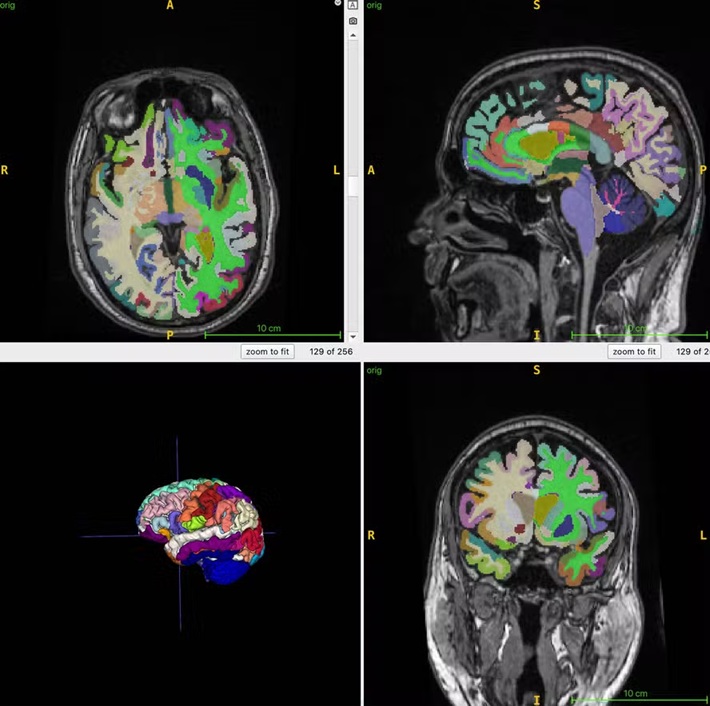

A idade cerebral é a estimativa computacional da idade cronológica a partir de uma ressonância magnética estrutural do cérebro.

A massa muscular, monitorada por ressonância magnética corporal, pode ser um marcador indireto para diversas intervenções que visam reduzir a fragilidade e melhorar a saúde cerebral. A idade cerebral prevista por imagens estruturais do cérebro pode fornecer informações sobre fatores de risco para a doença de Alzheimer, como a perda muscular.

Um algoritmo de inteligência artificial foi utilizado para quantificar o volume muscular total normalizado, a gordura visceral (gordura abdominal oculta), a gordura subcutânea (gordura sob a pele) e a idade cerebral.